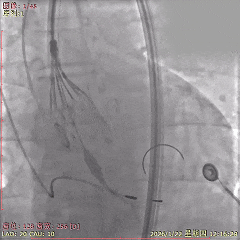

术中影像

初始造影确定无冠窦

瓣膜稳定释放至全展开

展开后造影,瓣膜位置可

多角度评估,确认瓣膜稳定

瓣膜脱钩后,无位移

最终造影,瓣膜位置可,无瓣周漏